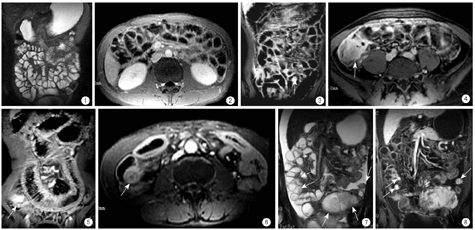

正常小肠肠腔在T1WI呈低信号,在T2WI呈显著高信号,图像类似于传统X线小肠造影(图1,图2)。T1WI的肠壁被周围抑制的脂肪低信号与肠腔液体的低信号清楚地描绘出中等信号,增强后呈中等均匀强化,并且显示更加清楚。肠壁厚度为2.0~ 3.0 mm,扩张良好的肠管直径为10.0~ 26.0 mm。

Crohn病MRI表现为多个节段肠壁增厚,强化增加,病变以肠系膜侧肠壁严重,肠管狭窄,病变可侵及肠管周围脂肪组织形成明显强化的蜂窝织炎、炎性肿块和瘘管(图3,图4,图5,图6)。GIST MRI表现为等T1、长T2信号的圆形肿块,边缘光整,增强后显著强化,中央坏死区不强化,可单发也可多发(图7,图8)。肠结核表现为病变连续性侵及回肠末段、盲肠及升结肠近端,肠壁明显增厚和强化增加,盲、升结肠短缩。1例十二指肠肿瘤肠壁明显增厚,在T1WI呈等信号,T2WI呈高信号,边界清楚,管腔狭窄,近端梗阻,MRI同时发现肝内多发转移灶,未手术切除获得病理诊断,仅行胃-空肠造瘘姑息治疗,临床诊断为腺癌。1例十二指肠结肠瘘表现为胃、十二指肠球部及横结肠内大量对比剂,而其余小肠对比剂充盈很少。小肠旋转不良见空、回肠及其血管均位于右腹部,肠系膜上动、静脉关系异常,回盲部位于中腹部。

MR小肠造影可清楚显示肠壁和肠腔。充满液体的小肠肠腔在T1WI呈低信号,在T2WI呈显著高信号,肠壁在T1WI被周围抑制的脂肪低信号与肠腔液体的低信号清楚地描绘出中等信号,增强后呈中等均匀强化,显示更加清楚。MR小肠造影应用最多的就是诊断Crohn病并评估其活动性,由于Crohn病好发于年轻患者,活动期和缓解期反复交替,在一生中需要多次影像学检查进行分期及评估疗效,多次X线和CT复查会接受大量射线辐射,增加发生肿瘤的风险,而MRI却是Crohn病反复多次复查的最佳选择。Crohn病的MRI表现为病变肠壁节段性增厚、强化增加,并且具有以肠系膜侧肠壁为重的偏心性的特点[1]。当病变穿透肠壁时,MRI可见肠系膜边缘模糊的蜂窝织炎和脓肿;若炎症穿透邻近肠管或腹壁,可形成肠管间的内瘘和肠管与体表的外瘘。因此,可显示肠管内、外病变的MR小肠造影可获得较传统X线小肠造影有关Crohn病更多的信息。

MRI对小肠肿瘤诊断敏感。本组病例均正确诊断出了小肠腺癌和GIST. 1例多发GIST,T2WI及增强T1WI清楚显示了小肠多发大小不等的肿瘤结节,最小的直径为8 mm,T1WI强化的肿瘤在低信号的肠腔和肠系膜的对比下呈明显高信号,很容易检出。Van Weyenberg等[11]对32例小肠肿瘤的MRI分析,敏感度和特异度分别达到0.94和0.97,总的诊断准确度达0.95,其诊断的最小小肠错构瘤型息肉大小为3 mm × 3 mm,最小腺瘤大小为4 mm × 7 mm。